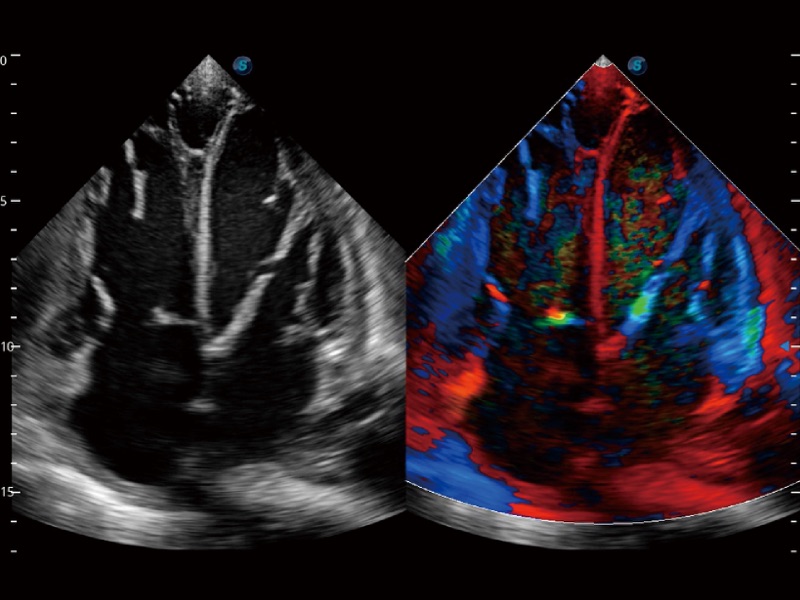

高分辨率血流成像技术提高了对低速血流信号的检测能力。在提高空间分辨率的同时,也克服了血流外溢现象,为用户提供更加真实的血流动力学信息。

心血管应用

支持运动和药物负荷协议、多心动周期存储选择,为临床观察心肌负荷状态下的室壁节段运动、评估心肌缺血状态提供更多的解决方案。

通过心肌识别技术和二维斑点追踪技术相结合,计算心肌各节段的应变应变率、速度、位移并以曲线图显示,实现整体或者局部心肌定量分析。同时可呈现牛眼图直观和准确诊断心肌的运动情况。

血管内中膜的厚度值是预测心血管疾病风险的重要指标,Auto IMT可以实现血管近场和远场内中膜厚度的自动测量,为临床提供快捷有效的诊断工具。